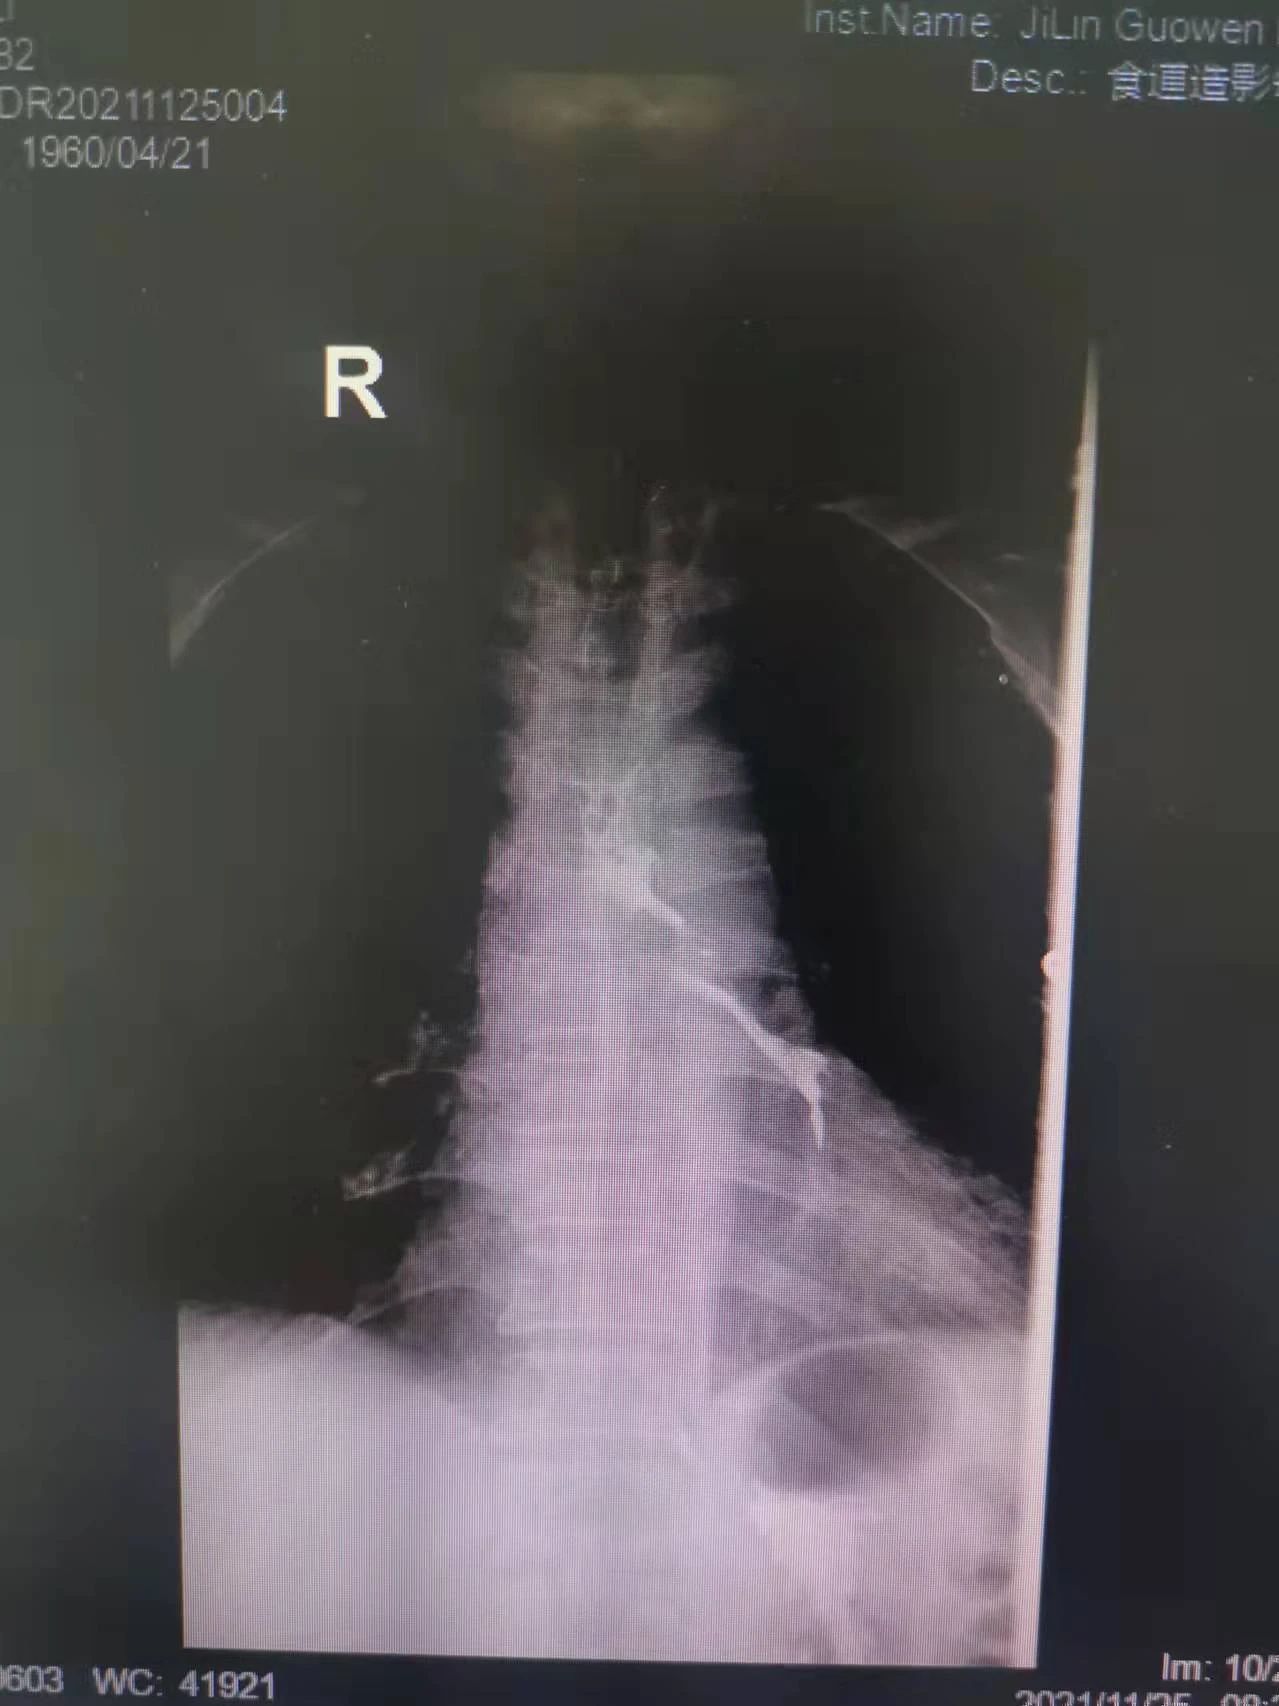

“大夫,我能喝點(diǎn)水么,我嗓子熱”今年61歲的付大爺患有食管惡性腫瘤。起初付大爺進(jìn)食時吞咽困難,每日進(jìn)食量極少,后隨著疾病的發(fā)展,付大爺進(jìn)食后伴隨劇烈嗆咳,經(jīng)系統(tǒng)檢查后,明確診斷為食管氣管瘺。為防止食物進(jìn)入氣管加重感染,付大爺聽從了醫(yī)生禁食水的意見?,F(xiàn)如今,付大爺每日不光承受著癌癥所帶來的疼痛,還要承受著禁食水后仿佛置身于沙漠般的口干舌燥。這段時間里,喝一口水這么一個小小的愿望對于他來說都已成奢求!有著正常食欲卻無法進(jìn)食,可以想象對于人的生理及心理帶來多么大的創(chuàng)傷。家屬眼見付大爺痛苦不已,也是焦急萬分。

在這種情況下,我院介入二科侯主任決定通過介入治療中的食管支架植入來幫助患者實現(xiàn)這個愿望。手術(shù)當(dāng)日,侯主任在機(jī)器的幫助下,將一根細(xì)細(xì)的導(dǎo)絲穿過腫瘤到達(dá)付大爺胃部,然后再沿著導(dǎo)絲,把壓縮好的支架放在腫瘤里面。通過后撤導(dǎo)管,把壓縮的支架打開,支架把腫瘤撐開,讓食管不再堵塞。有了支架的支撐,付大爺就可以自由地吃東西了,哪怕食管和氣管有溝通,因為支架覆蓋了腫瘤,通道堵住了,吃的東西也不會吸到肺內(nèi)造成感染。這時痛痛快快地吃上一頓,也不再是奢望!

手術(shù)很順利,付大爺也在術(shù)后第2天喝到了自己日思夜想的清水,露出了久違的笑容。從某種意義上講,介入食管支架置入術(shù)的成功實施,付大爺不能進(jìn)食的病已經(jīng)“治好”了,雖然從生理角度來說,付大爺可以通過終生使用腸內(nèi)營養(yǎng)來維持生存,但我們所做的是致力于給予患者更好的生存體驗,或者說是尊嚴(yán)。銘記并保持一名醫(yī)者的初心,我們要做的正如那句著名的墓志銘所說:有時去治愈,常常去幫助,總是去安慰。